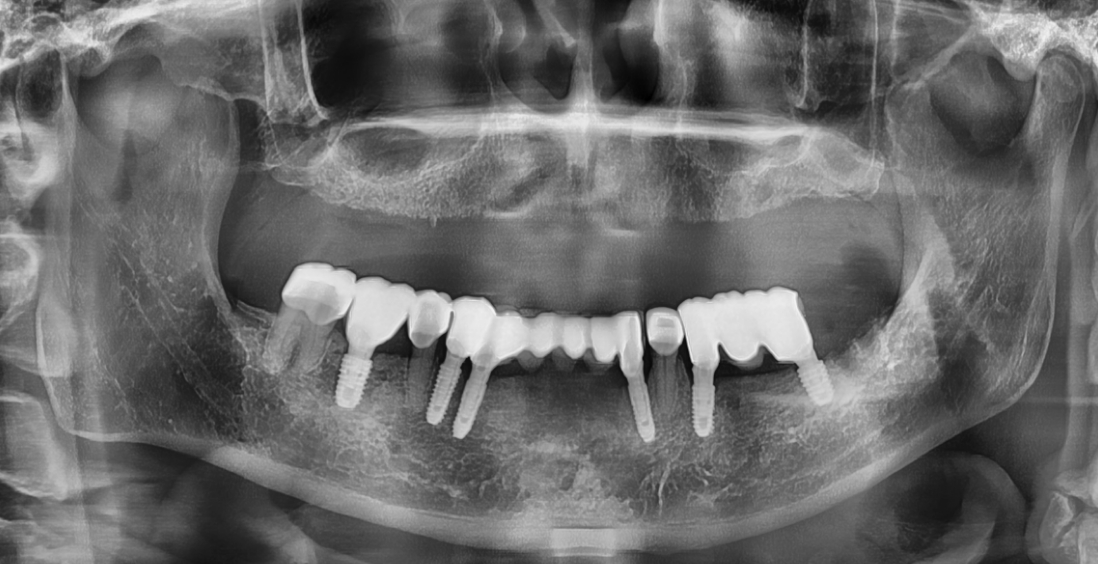

CASE 2 : 전체 임플란트 (치료기간 : 3개월)

*치료과정에서 부작용이 발생할 수 있으므로

정확한 진단과 수술이 요구됩니다.